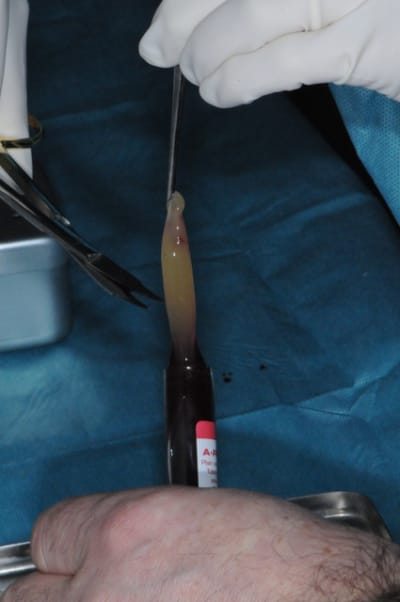

bon, la chir maintenant!

c'était ma première journée de reprise aujourd'hui. sympa pour commencer l'année, non ?

quelques photos de PRF pour relancer le sempiternel débat...

merci aux aficionados du " moi j'y crois pas au PRF" de garder ça pour un poste qu'ils pourront eux même créer sur ce BRRRÛLANT sujet...

bon, ça c'est fait!

4-5- un peu de A-PRF (the king !)

6- le plus important des sutures hermétiques et une gencive immobile en fin d'intervention